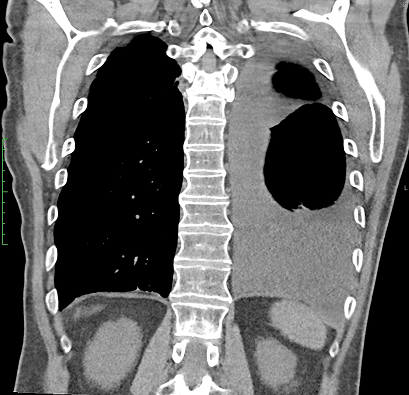

In a study patient, fluid occupying nearly half of the hemithorax at baseline was significantly reduced by 30 days and remained low at 60 days, demonstrating consistent drainage and lung re-expansion over time.

CT Baseline

30 Days

60 Days